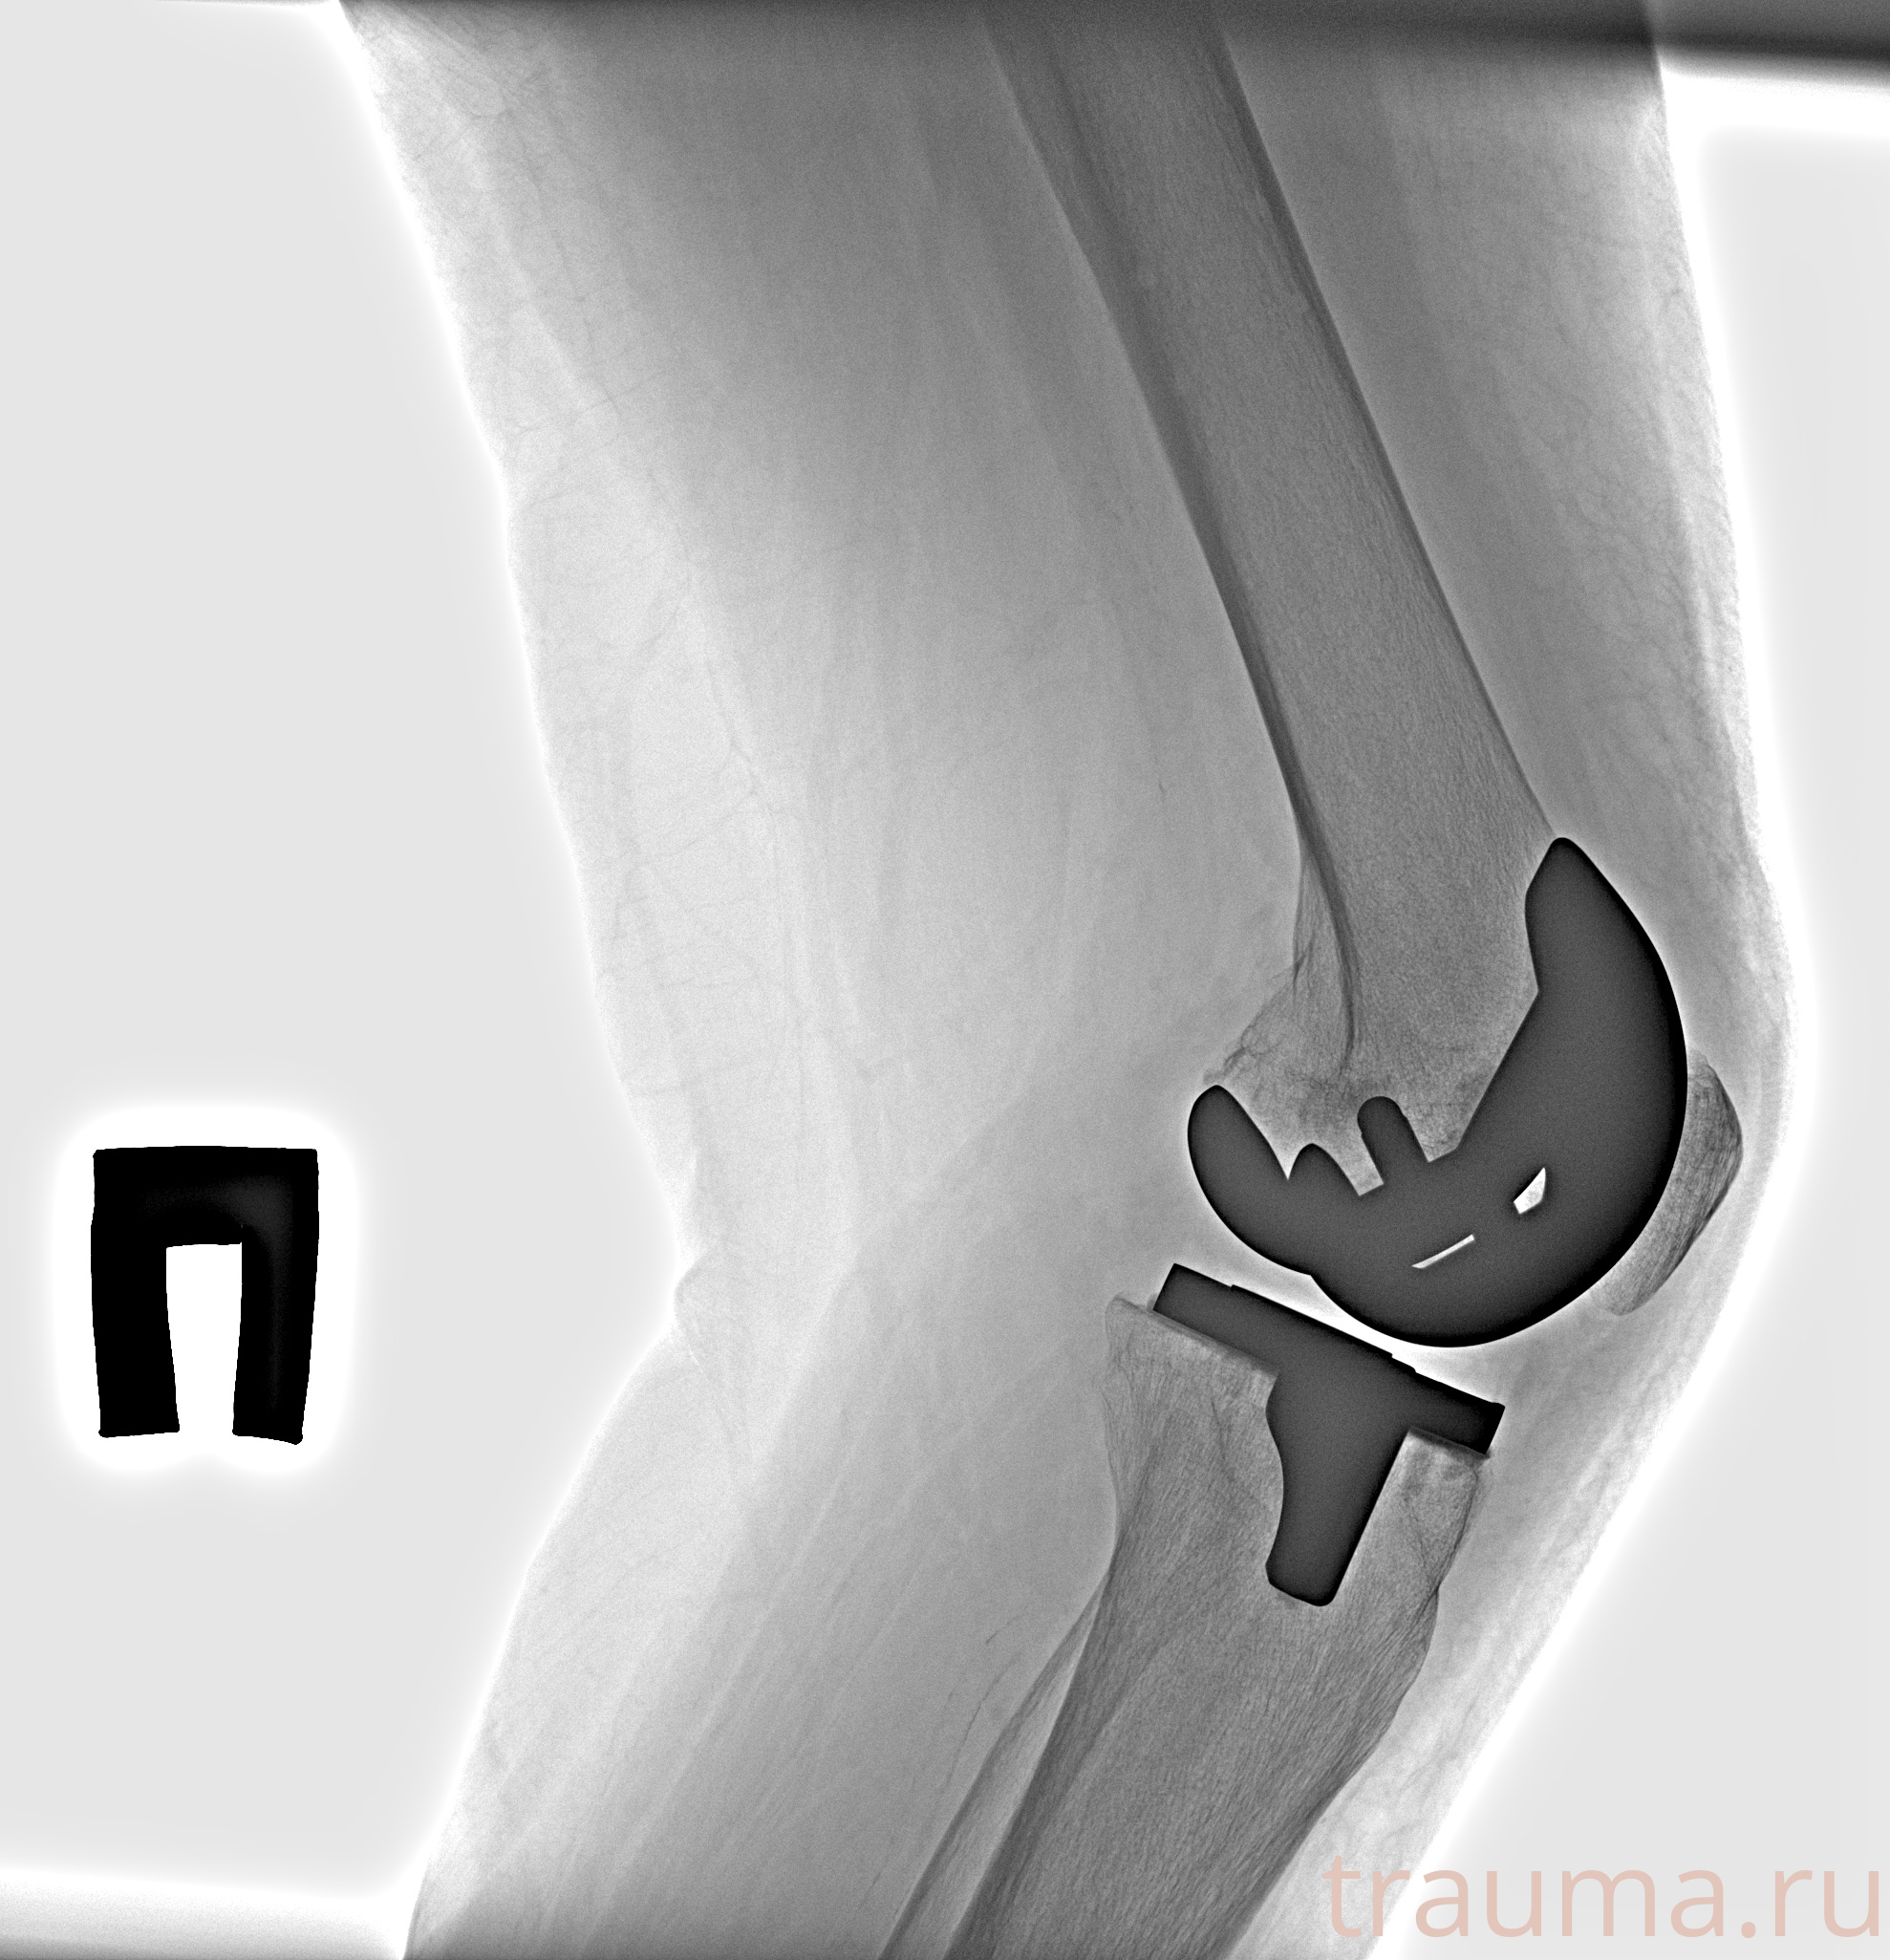

Рентгенограммы

Рентген на дому: по вашему адресу приезжает врач-рентгенолог, травматолог-ортопед с мобильным рентгеновским аппаратом, проводит диагностику травмы или заболевания, делает необходимые рентгенограммы, дает рекомендации по дальнейшему лечению. Получить качественные снимки в домашних условиях возможно благодаря уникальной методике, разработанной МосРентген Центром для института  Склифосовского